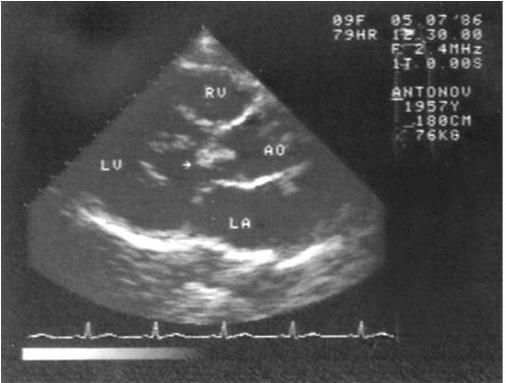

Рис. 1.7. Эхокардиограмма больного инфекционным эндокардитом. Вегетация (указана стрелкой) на аортальном клапане

Наиболее информативным инструментальным методом исследования является эхокардиография, особенно транспищеводная, выявляющая достаточно мелкие вегетации (не менее 5 мм) и сопутствующие изменения клапанного аппарата (рис. 1.7). Вегетации обычно появляются не раньше, чем через 2 недели после начала заболевания и длительно сохраняются после выздоровления (несколько месяцев). Ультразвуковое исследование, как правило, выявляет увеличение размеров селезенки.

Диагноз инфекционного эндокардита считается достоверным при наличии лихорадки, шума в сердце, эмболий, бактериемии, вегетаций по данным эхокардиографического исследования. При необнаружении вегетаций диагноз оценивается как вероятный, а наличие лихорадки неизвестного генеза в сочетании с эмболиями и/или шумом в сердце является критерием возможного инфекционного эндокардита.